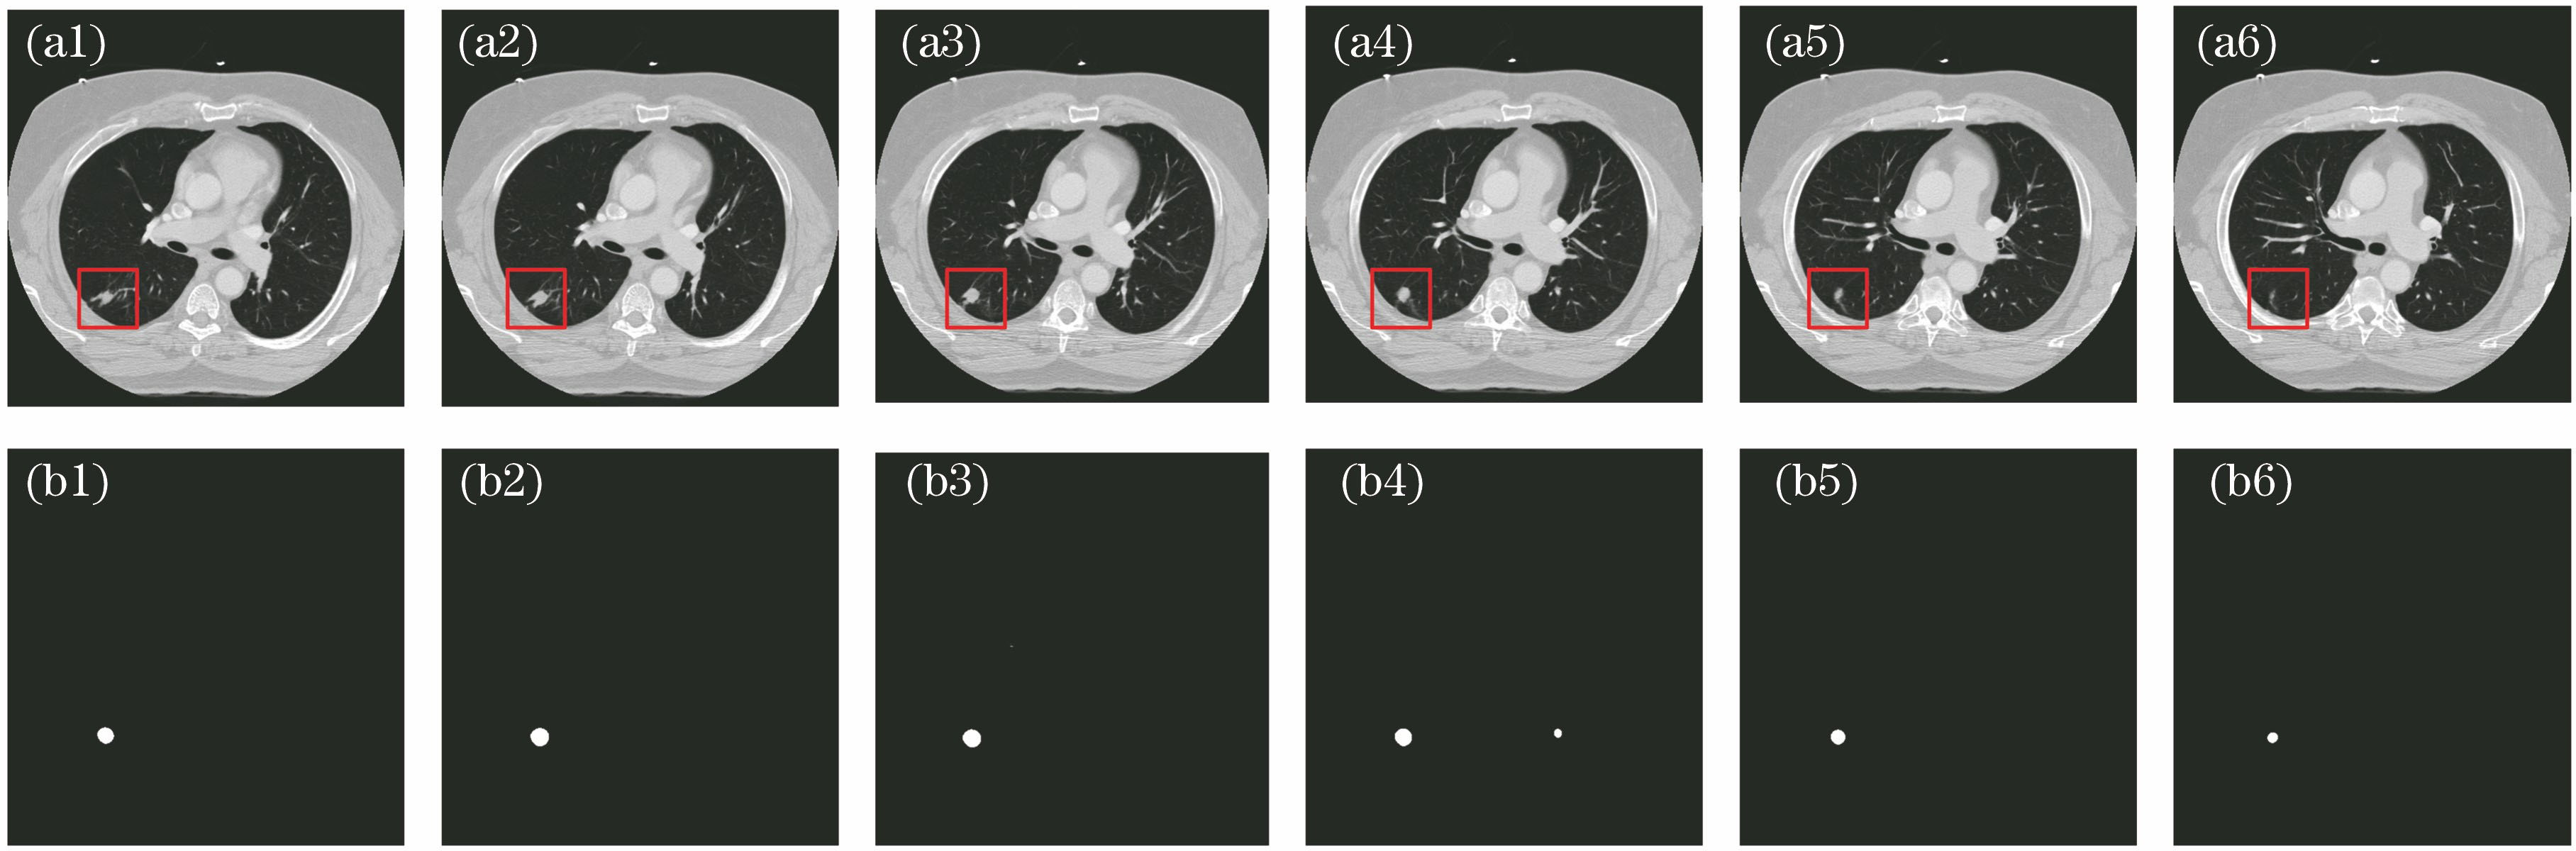

图 2. CT切片序列原图与U-net预测图。(a)原图;(b)预测图

Fig. 2. CT slice original images and U-net prediction images. (a) Original images; (b) prediction images